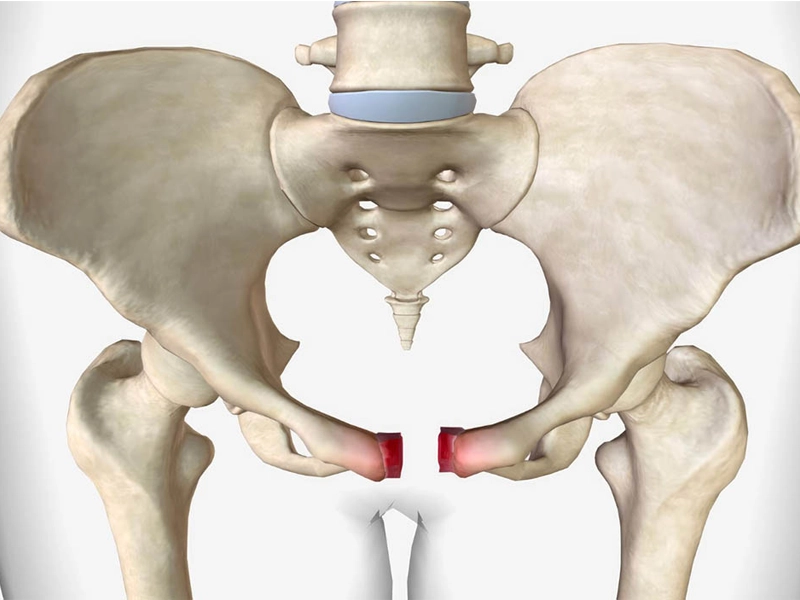

ترک خوردگی استخوان لگن به آسیب جزئی یا شکستگی مویی در یکی از استخوانهای لگن گفته میشود که معمولاً به دلیل ضربه مستقیم، سقوط، تصادف یا فشار مکرر روی استخوان ایجاد میشود. این آسیب میتواند در هر سنی رخ دهد، اما در سالمندان بهدلیل پوکی استخوان و در ورزشکاران بهدلیل فعالیتهای سنگین بیشتر دیده میشود. […]